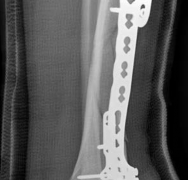

With the articular surface reconstituted, the surgeon's focus shifts to bridging the complex metaphyseal-diaphyseal dissociation. A pre-contoured anatomical locking plate is slid submuscularly or subcutaneously along the diaphysis using a MIPPO technique. The plate is positioned on the anterolateral or medial surface, depending on the preoperative plan and soft tissue constraints.

Image

The distal portion of the plate is secured to the reconstructed articular block. It is imperative that the distal locking screws are placed parallel to the joint space, forming a rigid subchondral raft that supports the articular cartilage. Fluoroscopy is utilized extensively to ensure no screws have penetrated the joint. Once the distal block is secured to the plate, the diaphyseal segment is aligned. Length, alignment, and rotation are restored using manual traction or the femoral distractor. The proximal portion of the plate is then secured to the diaphysis using a combination of non-locking screws (to pull the bone to the plate) and locking screws (to create a fixed-angle construct). The working length of the plate is maximized by leaving several screw holes empty over the zone of comminution, promoting secondary bone healing.